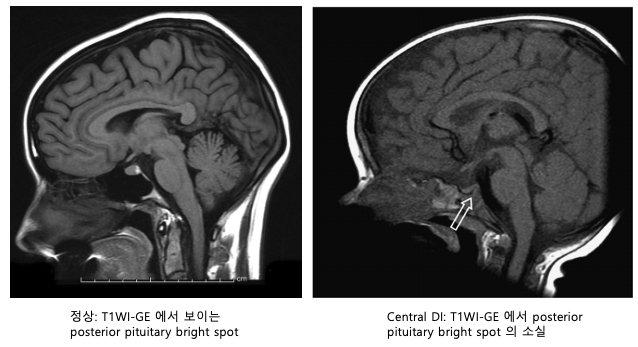

• 5. 뇌 MRI (Sella MRI)

• AVP-D(중추성)에서 뇌하수체 후엽의 고신호강도(bright spot) 소실 확인

• 줄기 비후(stalk thickening) 등 구조적 원인 감별